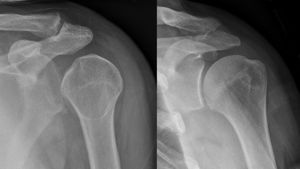

النقطة المضيئة تشير لخلع الكتف الخلفي على الجهة اليسرى. على اليمين، نفس الكتف بعد إجراء عملية الرد.

خلع الكتف الخلفي من الحالات الشائعة، وعادة ما يحدث بسبب انقباض العضلات بسبب صدمة كهربائية أو التشنج.[5] وقد يحدث نتيجة عدم توازن العضلاات المحيطة بالكتف. عادة ما يحمل المريض ذراعه بصورة دائرية إلى الداخل، كما تضعف العضلات المحيطة بالكتف مع حالة إصابة واضحة في النتوء الغرابي.

قد يحدث الخلع الخلفي لأسباب غير معروفة، وخاصة بين كبار السن[11] وفي حالات الصدمة الغير واعية.[12] في دراسة لمجموعة من 40 حالة، لوحظ أن الفترة بين الإصابة والتشخيص تصل إلى عام.[13]